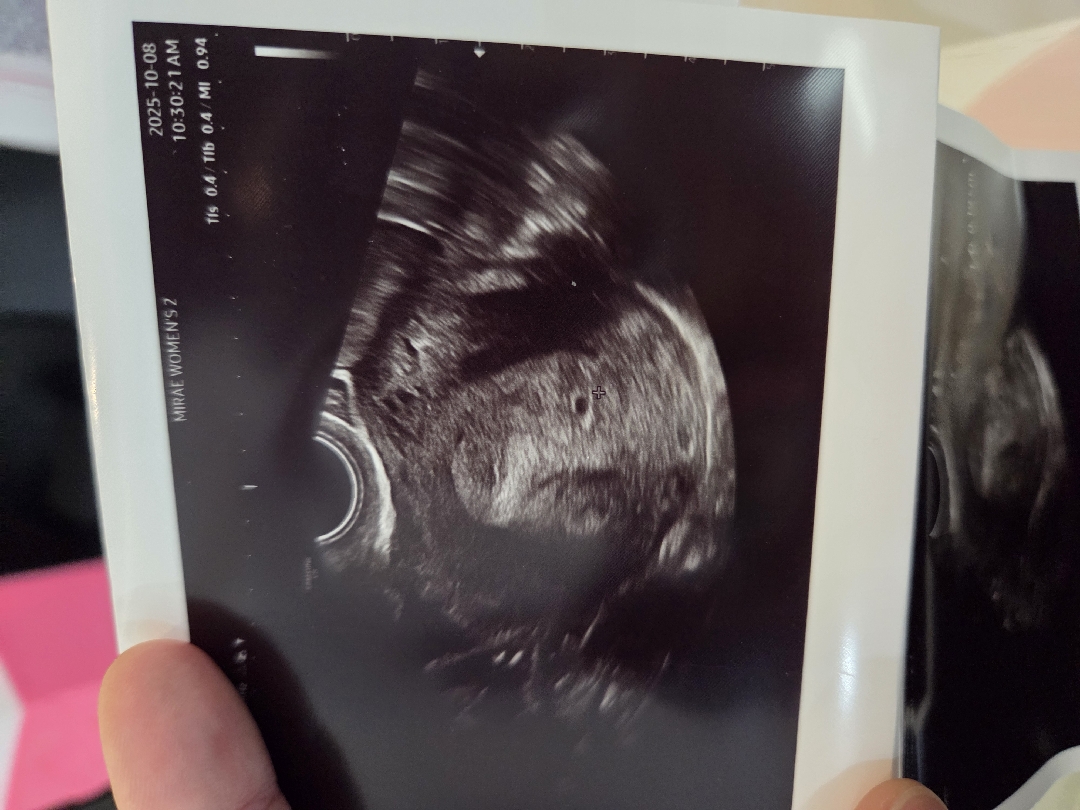

아기집 맞겠죠?? 5주1일

의사선생님도 일찍오셨다고 너무 작아서 한참 봤다고하시더라구요.. 그래도 임신확인서 끊어주신거보면 확실하다는거죠? 전 피검사는 따로 안하시던데 왜일까요...ㅠㅠ 다음주에 가면 커져있겠죠?ㅠㅠ 너무 걱정되네요 저같이 작게 보이는 분들도 계세요??? ㅠㅠㅠ